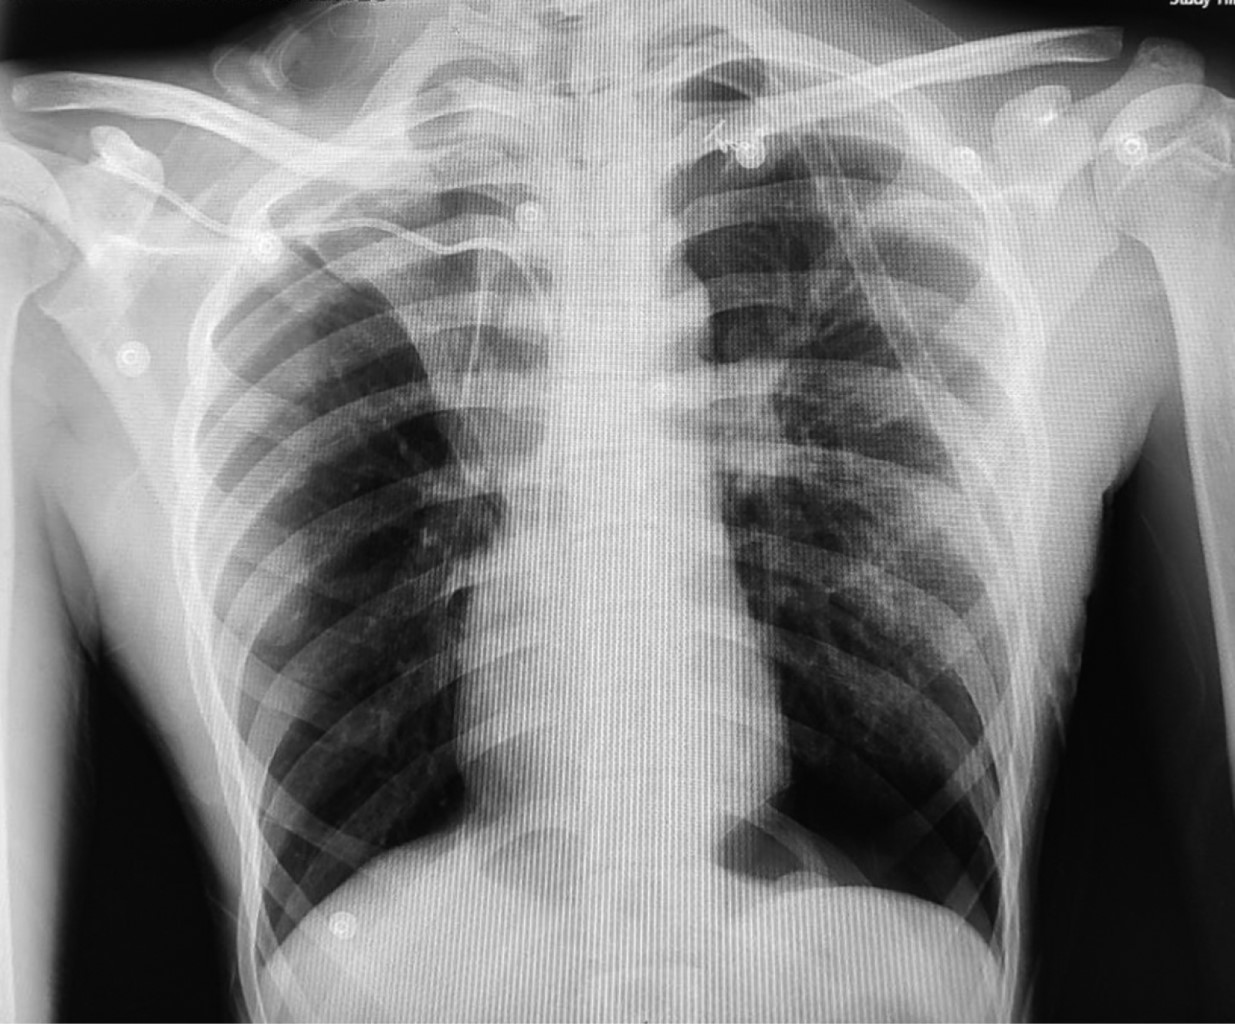

Inicia padecimiento con disnea en reposo, dolor torácico tipo pleurítico, por lo que acude a urgencias, a la exploración física se encontraba con reducción de los movimientos torácicos, hiperresonancia a la percusión e hipoventilación del hemitórax izquierdo, se realiza radiografía de tórax observándose neumotórax izquierdo, por lo que se decide colocación de sonda endopleural, se ingresa para vigilancia, muestra mejoría clínica y radiográfica y es egresado por mejoría.

El tres semanas después acude al servicio de urgencias refiriendo dolor en hemitórax izquierdo de dos días de evolución, de inicio súbito, transflictivo, así como disnea en reposo, a la exploración física con hipoventilación de hemitórax izquierdo e hiperresonancia a la percusión, en la radiografía se observa neumotórax recidivante (Figura 1) y se coloca sonda endopleural, con adecuada expansión pulmonar (Figura 2) y buena evolución clínica, siete días después se realiza prueba con sonda pleural a sello, presentando disnea y dolor torácico, en radiografía de control se aprecia neumotórax izquierdo recidivante (Figura 3), por lo que se solicita tomografía computarizada observándose persistencia de neumotórax y bulla apical izquierda, por lo que se inicia protocolo quirúrgico para toracoscopia.

Figura 1